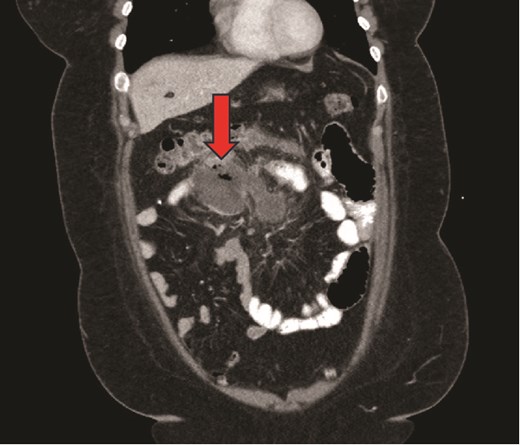

Our patient is a 38-year-old female with a medical history of cerebral palsy, congenital cerebral ventricular dilation and hydrocephalus with VP shunt placement in infancy, sleep apnea and morbid obesity (body mass index (BMI) 43 kg/m2) who underwent laparoscopic Roux-en-Y gastric bypass (LRYGB) and was discharged on postoperative day (POD) #1. On POD#15, she sustained a syncopal event and presented to the emergency department. She was found to be tachycardic to 105 beats/min with epigastric tenderness and a leukocytosis of 15.6 (thou/μL). Computed tomography (CT) scan revealed a 4.8 × 10.1 cm air- and fluid-containing collection worrisome for abscess versus contained small bowel perforation (Fig. 1). She underwent diagnostic laparoscopy converted to exploratory laparotomy, revealing an infected hematoma with abscess in the mesentery of the proximal common channel and adjacent ischemic bowel without evidence of perforation. She underwent drainage of the abscess and resection of the compromised bowel, including her jejunojejunostomy (JJ) and 40 cm of the common channel. A new JJ was created. Intraoperatively, two VP shunt catheters were inspected and consultation from neurosurgery was obtained (Fig. 2). One shunt was determined to be nonfunctional and was removed. The functional shunt was externalized. Postoperatively, she was admitted to the intensive care unit for shunt monitoring, placed on cefepime, metronidazole and vancomycin, and her shunt was serially cultured. Intraabdominal fluid cultures from the operating room were polymicrobial, including Klebsiella oxytoca, Citrobacter freundii complex, Enterococcus faecalis, Parvimonas micra, and Prevotella. After persistently negative shunt cultures and 12 days of intravenous antibiotics, her shunt was re-internalized on POD#14 (POD#28). She completed a 14 day total course of antibiotics and was discharged home. She was most recently seen for an annual visit and is doing well, having lost 33% of her total body weight, and 58% of her excess body weight.